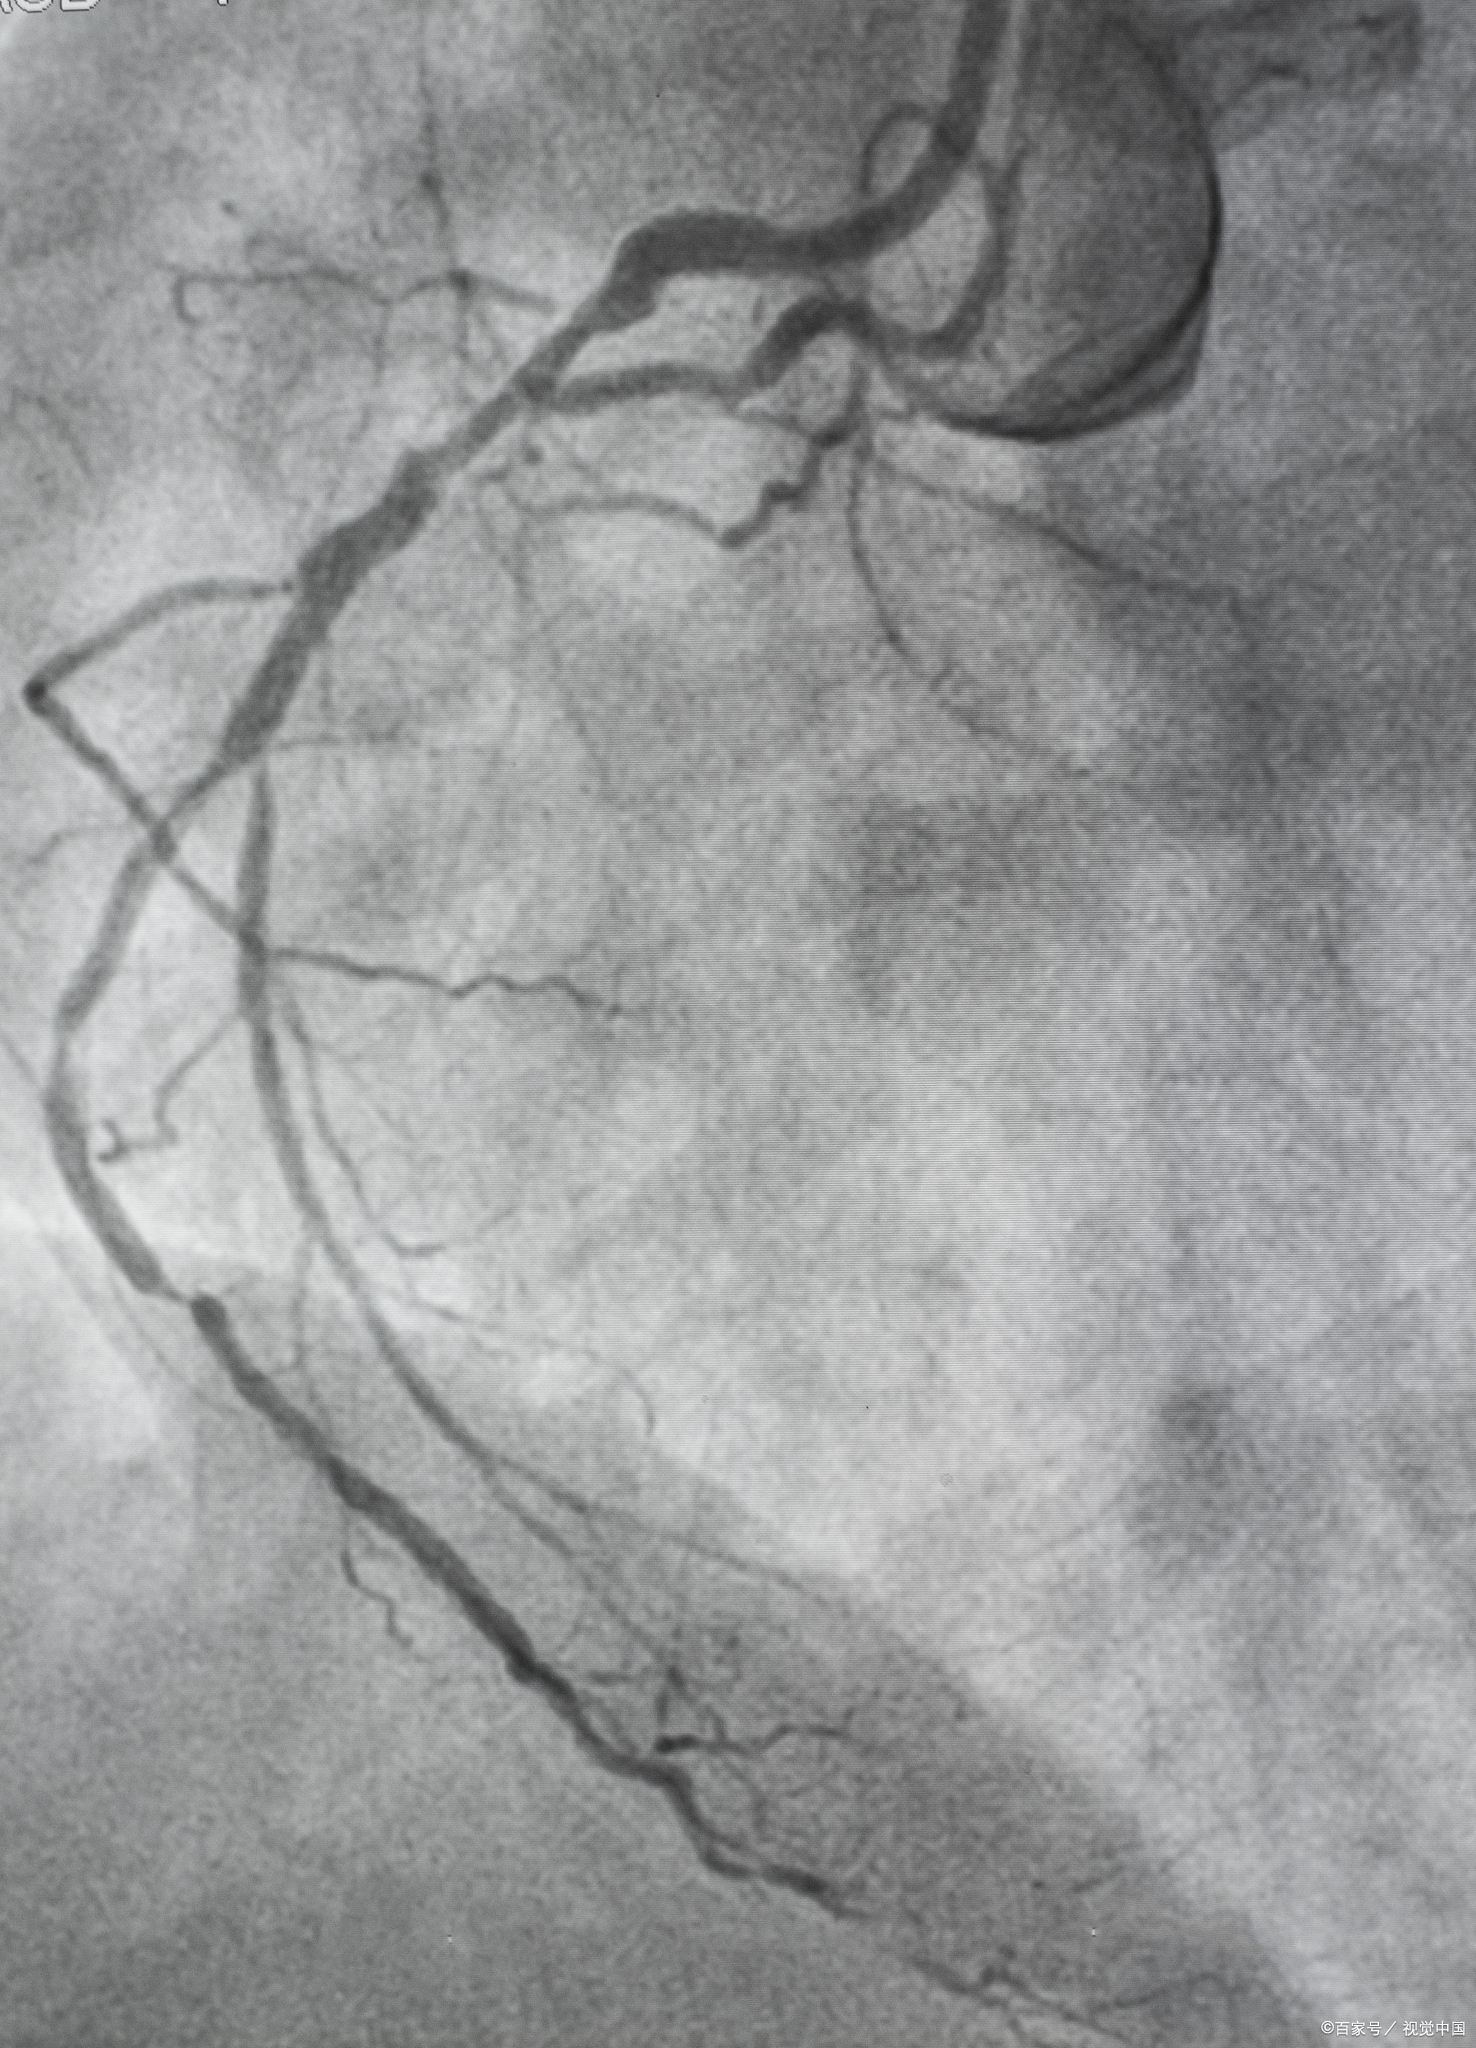

冠状动脉造影是一种微创的介入手术,具体做法如下选择外周动脉通常选择右侧的桡动脉,即右手腕部的血管如上臂血管条件不佳或需进行复杂操作,则可能选择大腿根部的股动脉插入导管在选定的动脉位置做一小切口将导管插入该动脉,并沿着动脉一直送到心脏表面的冠状动脉注射造影剂通过导管向冠状动脉内注射造影剂造影剂会使冠状动脉的形态在X光下清晰显示出来注意冠状动脉造。

X光观察在X光线下,观察造影剂在冠状动脉内的流动情况,从而判断冠状动脉是否存在狭窄闭塞或者斑块等问题整个检查过程 如果操作熟练,一般15分钟左右就可以完成整个心脏血管造影检查检查的意义 冠状动脉的造影检查主要为患者进一步做冠状动脉增强进行前期的准备 若发现血管有重度狭窄明显闭塞或。

冠状动脉血管造影检查是通过以下步骤进行的局部麻醉与穿刺选择在人体的桡动脉或股动脉进行局部麻醉对麻醉部位进行局部穿刺,以便引入导管导管引入与造影剂注射导管通过桡动脉或股动脉进入,并沿着动脉路径直达冠状动脉的开口处向冠状动脉内注射造影剂,以便在X线下清晰显示冠状动脉的形态X线观察与。